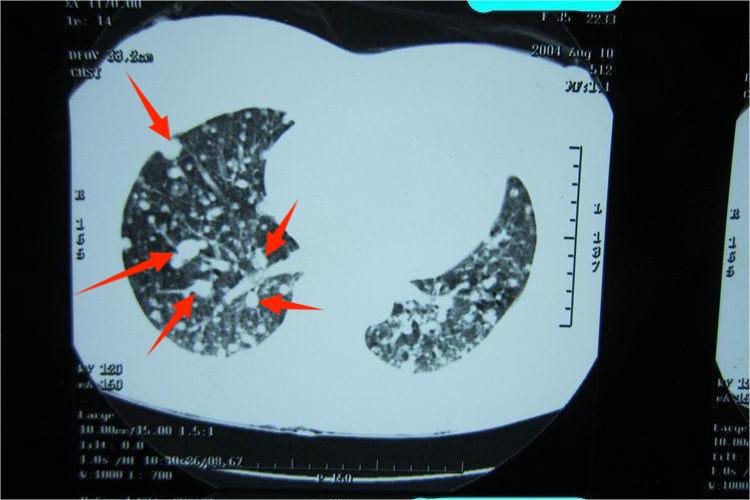

28例矽肺X线征象分析

矽肺是由于长期在含有二氧化硅的环境中工作,而引起肺弥漫性纤维性病变的一种职业病。笔者随机抽取本院职业病科近年经确诊的28例病例,对其胸部X线征象进行分析、研究结果如下。临床资料1、...[详细]